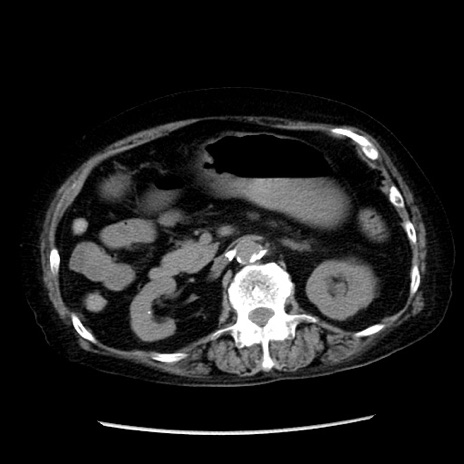

症例14(横断像)

【症例】 90歳代女性

【主訴】 腹痛・嘔吐

【現病歴】今朝から左側腹部痛を認めた。 経過観察していたが、嘔吐を認めたため来院。

【既往歴】 子宮癌術後

【身体所見】 意識清明、BP 127/54mmHg、P 98bpm Sp02 95%(RA)、BT 35.8°C、腹部平坦・軟腸ぜん動音聴取良好、右下腹部圧痛(+) 反跳痛なし

【データ】WBC 9800、CRP 0.46